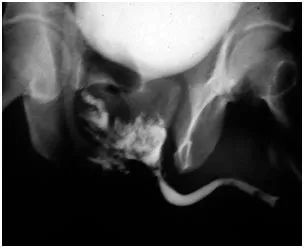

- Gold Standard: Retrograde Urethrogram (RUG) is the definitive initial test.

- Performed before any Foley catheter attempt in suspected cases.

- Positive Finding: Extravasation of contrast dye confirms and localizes the urethral tear.